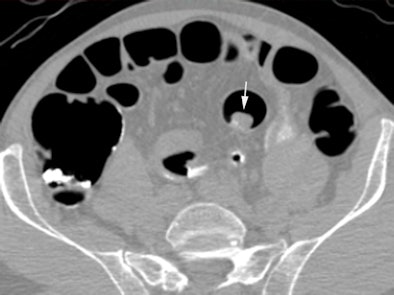

| Above, supine virtual colonoscopy image shows a 20-mm adenoma (arrow) in the sigmoid colon. Below, fused PET/CT in the same patient shows an area of intense F-18 FDG uptake corresponding to the 20-mm adenoma. A small amount of misregistration is present. Arrowhead points to ureteric activity. All images courtesy of Dr. Stuart Taylor. |

Of the 14 polyps that were 6 mm or larger in diameter, 12 (86%, 95% CI: 67%-100%) were avid for F-18 FDG, including all of the lesions 10 mm or larger (mean standardized uptake value [SUV], 10.1), Taylor and his team wrote. Moreover, the group found no significant difference in mean SUV for adenomas with (mean, 12.7) and without (mean, 7.4) high-grade dysplasia (p = 0.10).

CTC's sensitivity for polyps 6 mm or larger of 92.9% (95% CI: 79.4%-100%) did not improve with the addition of PET. However, the combined exam did improve the per-patient positive predictive value for a polyp 10 mm or larger from 73% (95% CI: 39%-92%)to 100% (95% CI: 60%-100%).